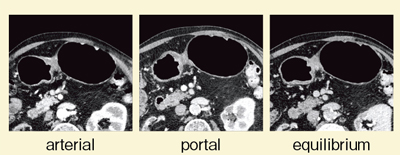

症例1は,胃角部V型胃がんである。胃角部小彎側のやや後壁寄りに,かなり深い潰瘍が認められた。DEで撮影したところ,逐次近似画像再構成法であるSAFIREを併用したcomposite imageにて,病変部が最も明瞭に描出された(図1)。ダイナミックCTを施行したところ,動脈相では80kVで粘膜が,門脈相では80kVで腫瘍が最も良好に濃染した(図2)。また,Liver VNCでiodine imageを評価したところ,50〜100%の画像で胃壁が最も良好に濃染しているが,腫瘍は濃染していなかった(図3)。さらに,SAFIREを用いたcomposite imageでは,特に平衡相で,どの部分に多く造影剤が流入しているかが理解しづらい(図4)。そこで,iodine imageを作成したところ,門脈相から平衡相にかけて,後壁部分がきわめて良好に濃染していることがわかった(図5)。これにより,後壁中心に線維化の強い胃がんと診断できた。本症例は潰瘍があるため,深達度診断が難しいが,胃壁外の血管の拡張も明瞭に認められ,進行がんの可能性があると思われる。

![]() 図3 症例1:Liver VNCによるiodine/composite image |